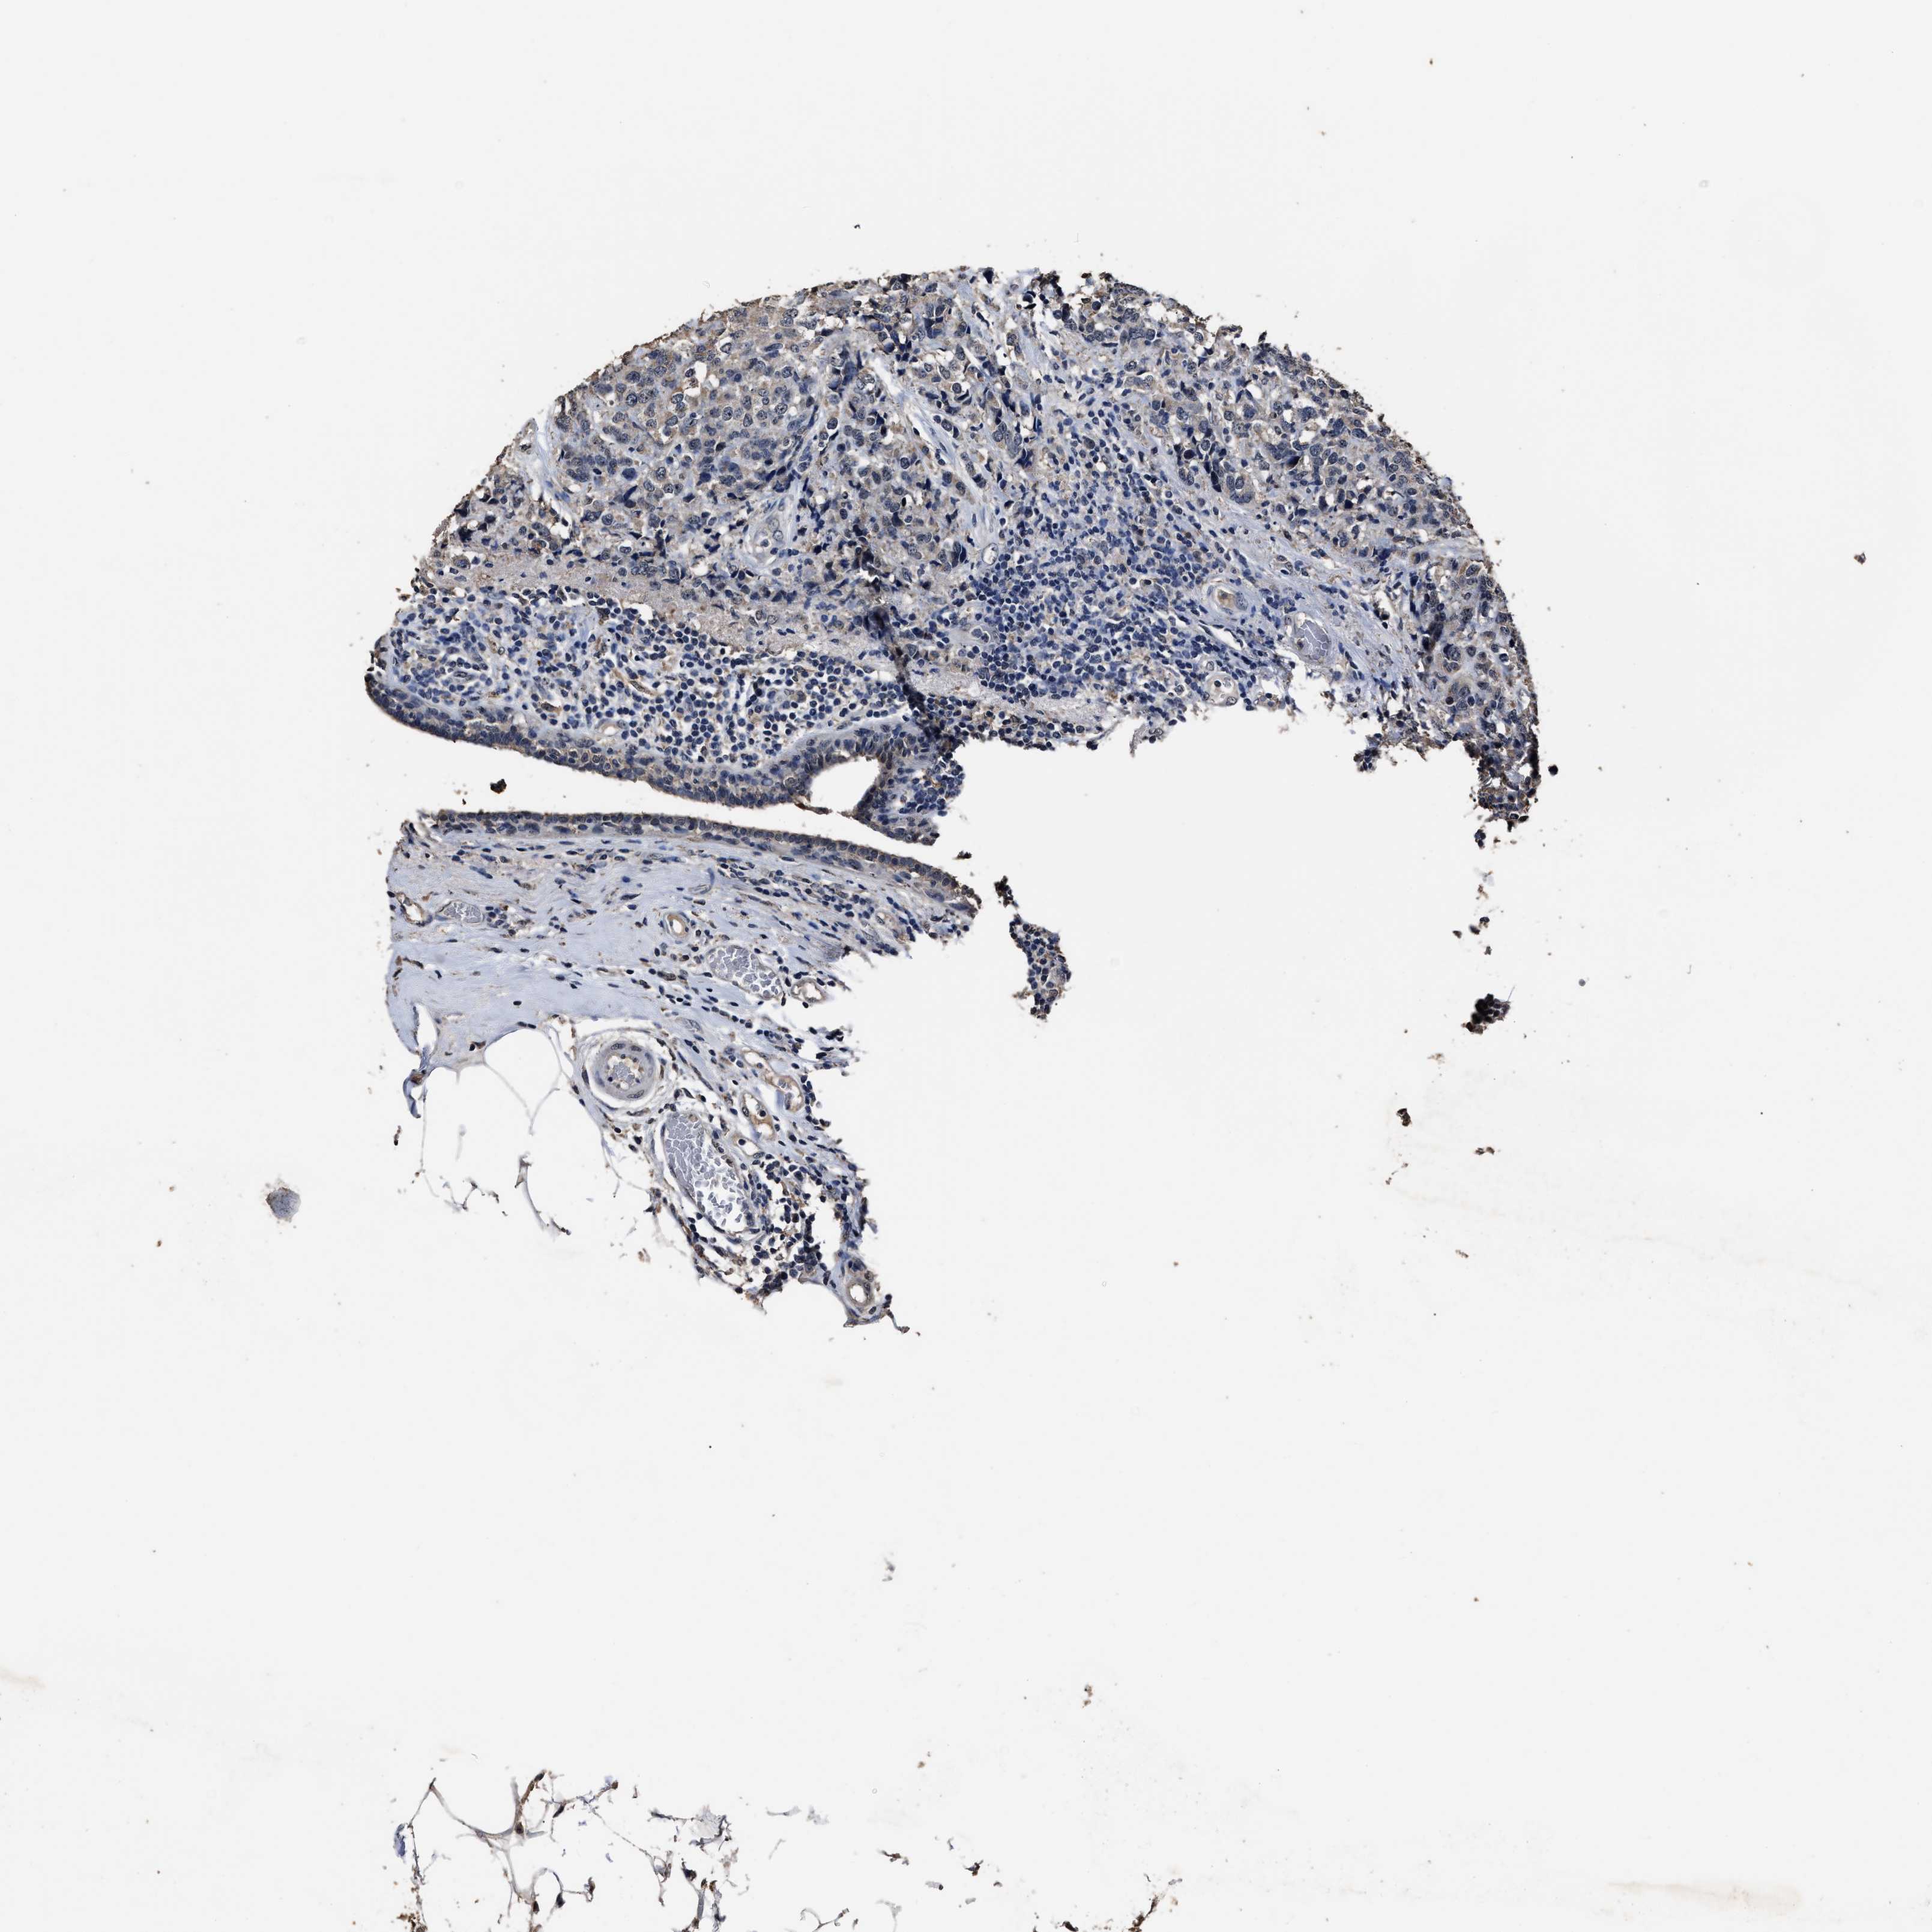

CANCER BREAST CANCER Show tissue menu

BRCA TCGA BRCA VALIDATION PROTEIN EXPRESSION